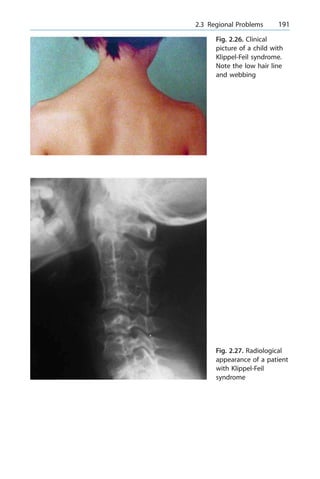

chance of AVN/nonunion high (90%) that many choose primary

(open or percutaneous) fixation via dorsal approach

n For the common mid-third waist fracture, there is a recent trend to-

wards percutaneous screw fixation. There is as yet no long-term result

but should be appealing for patients who have to return to their work

early (sometimes for financial reasons) or are involved in competitive